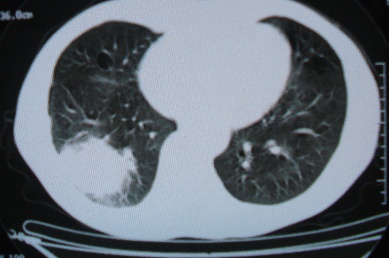

ct10716,男,59岁。发热咳嗽一天,咯血一次入院。

病灶中心有低密度,气体,病灶周围炎性浸润可能为肺脓肿,量体温、查个痰就是了,但肺脓肿一般都多少会有点兄水的。左肺下局部密度减低,小叶中心肺气肿。

病灶边缘较模糊,中心见低密度影及少量气影,宽基与胸膜相连,周围见炎性浸润,考虑右下肺脓肿。

病灶边缘较模糊,中心见低密度影及少量气影,宽基与胸膜相连,周围见炎性浸润,考虑右下肺脓肿。建议治疗后复查。

右下肺病灶,边缘模糊,中心见低密度坏死区及气体影,结合病史较短,以发热为主,考虑右下肺脓肿,建议抗炎治疗后复查。